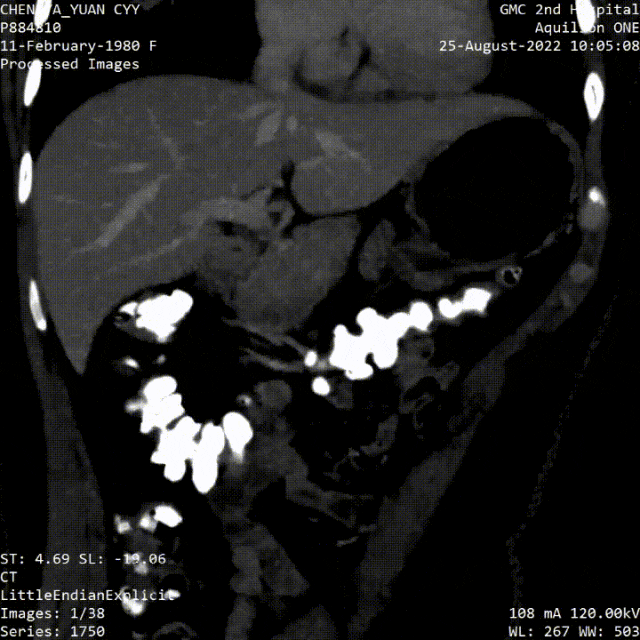

Case 1

女性,42岁

因“反复左下肢肿胀5月余,下腔静脉滤器植入术后1月余” 入院。

患者1月前因“左下肢深静脉血栓形成”在外院行下腔静脉滤器植入术,先后两次行下腔静脉滤器取出术均未成功。

查体:双下肢皮温暖,左下肢肿胀,非凹陷性,双股动脉、腘动脉、足背动脉搏动可及。

既往史:2018年行全子宫切除术。

入院彩超:下腔静脉及双下肢静脉无血栓

外院两次腔内取滤器均告失败,且滤器变形,头端突入右肾静脉

图为:入院CT及增强